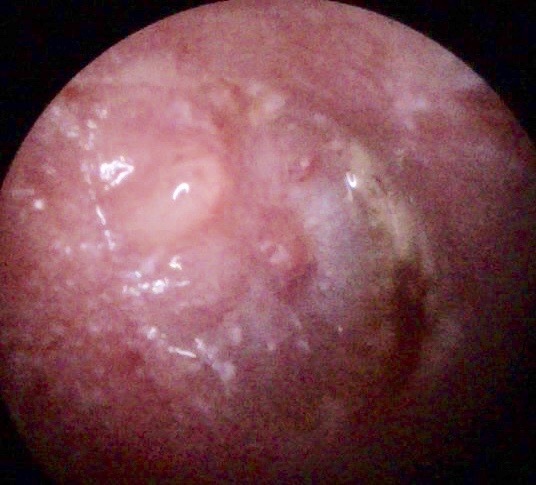

CSOM

Otitis media

Tympanic Membrane